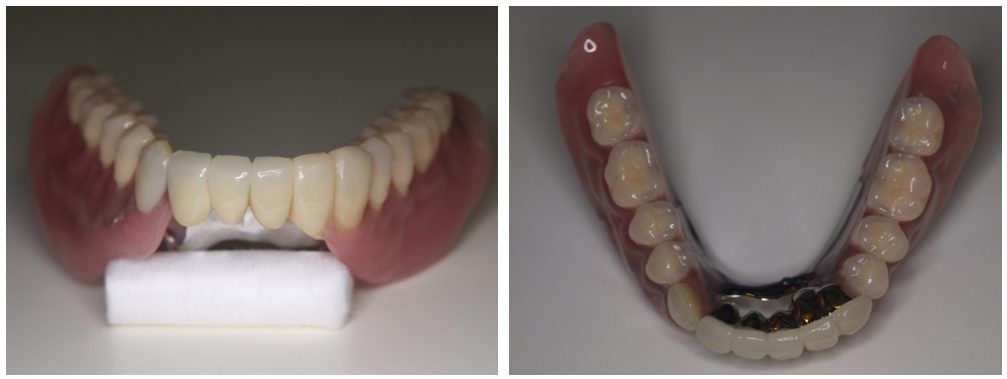

| 主訴 | 60代女性 バネを掛けている歯がグラグラする、インプラント治療はしたくない、バネが見える義歯は嫌だ |

| 治療内容 | インプラント治療、セラミック治療、金属床コーヌス義歯(部分入れ歯)を行いました。 |

| 治療費 | 1,200,000円(税込み) |

| 治療期間 | 4か月 |

| 治療回数 | 15回 |

| 想定されたリスク | 残存歯が少なく、義歯にすると残存歯(前歯)に負担がかかるリスクがあった |